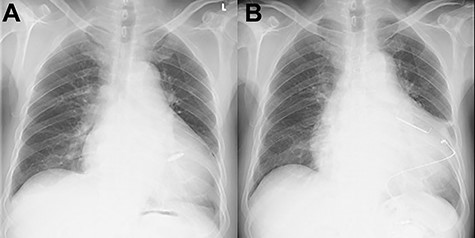

Chest X-ray findings; (A) immediately post-implantation of Micra (B) after tricuspid valve repair and implanted epicardial PM system.

The patient had an uneventful postoperative course during his hospital stay and was discharged on the 22nd day after the operation (Fig. 2B). Postoperative TTE showed trace TR. Six months after the operation, the patient was undergoing outpatient clinical monitoring and was reportedly well.